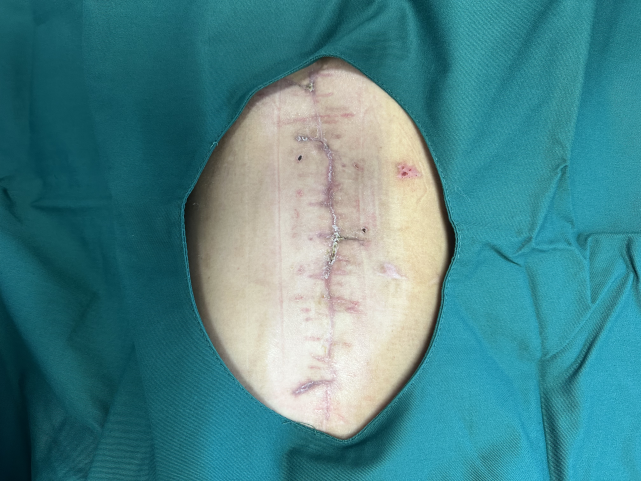

恢复后的创面

经数月精心治疗护理

郭女士腹部难愈的创面完全愈合

流脓症状消失